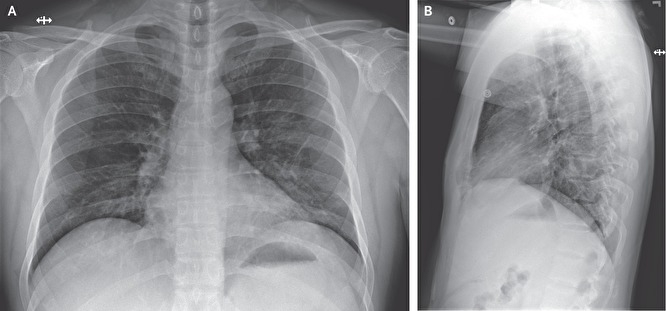

Во время первого осмотра температура пациента составляла 37,2 градуса, давление – 134/87 мм рт. ст., пульс – 110 ударов, а частота дыхания – 16 вдохов за одну минуту. Во время прослушивания легких медики обнаружили хрипы, однако на рентгеновском снимке грудной клетки не было замечено каких-либо отклонений.

Медики продолжали поддерживающее лечение, давая пациенту жаропонижающее, средство от кашля и физраствор. На третий день полные анализы крови выявили изменения в функции печени, лейкопению и легкую тромбоцитопению. Рентген снова не показал аномалий.

На пятый день рентген показал пневмонию в нижней доле левого легкого. На шестой день в больнице пациенту начали давать через нос дополнительный кислород, также назначили лечение цефепимом и ванкомицином. Также на шестой день рентген показал помутнения в обеих легких, что считается признаком атипичной пневмонии.